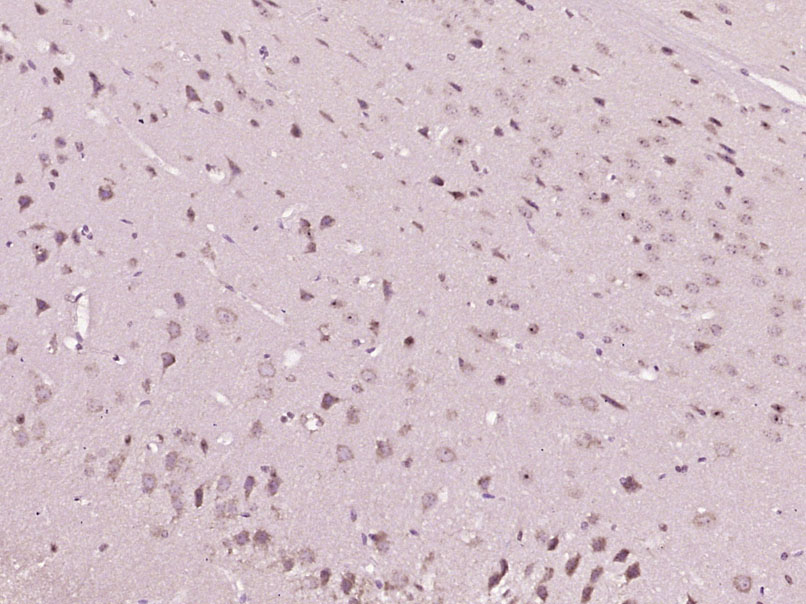

| 组织特异性 | Widely expressed. Highly expressed in brain, placenta and prostate. Expressed in tumor cells such as hepatoma cells LO2, cervix carcinoma cells HeLa, ovary cancer cells Ho8910 and chronic myelogenous leukemia cells K562, but not in other tumor cells such as epidermoid carcinoma (A431). Undetectable in most normal lung tissues, widely expressed in lung cancers. |

| {IHC-P} | {1:100-500} |